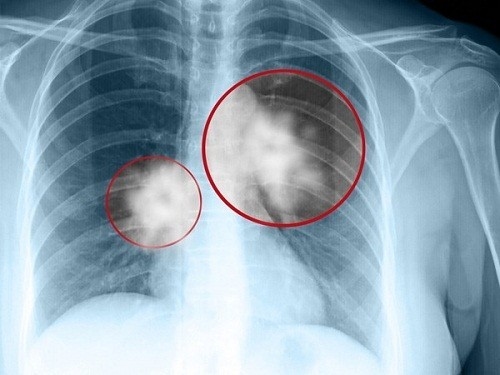

Chụp X-quang phổi là phương pháp chẩn đoán hình ảnh đầu tiên thường được chỉ định trong chẩn đoán các bệnh lý về hô hấp, trong đó có ung thư phổi. Tuy nhiên đối với những trường hợp khố u còn nhỏ thì không thể phát hiện được qua chụp X-quang phổi. Lúc này người bệnh cần chụp cắt lớp CT mới có thể phát hiện những khối u có kích thước nhỏ, có đường kính xấp xỉ 1mm.

Khi khối u có kích thước to hơn, chụp X-quang phổi có thể phát hiện khối u. Tuy nhiên để có phương pháp điều trị bệnh phù hợp thì cần phải làm thêm các phương pháp chấn đoán khác để xác định mức độ bệnh và giai đoạn bệnh cụ thể.